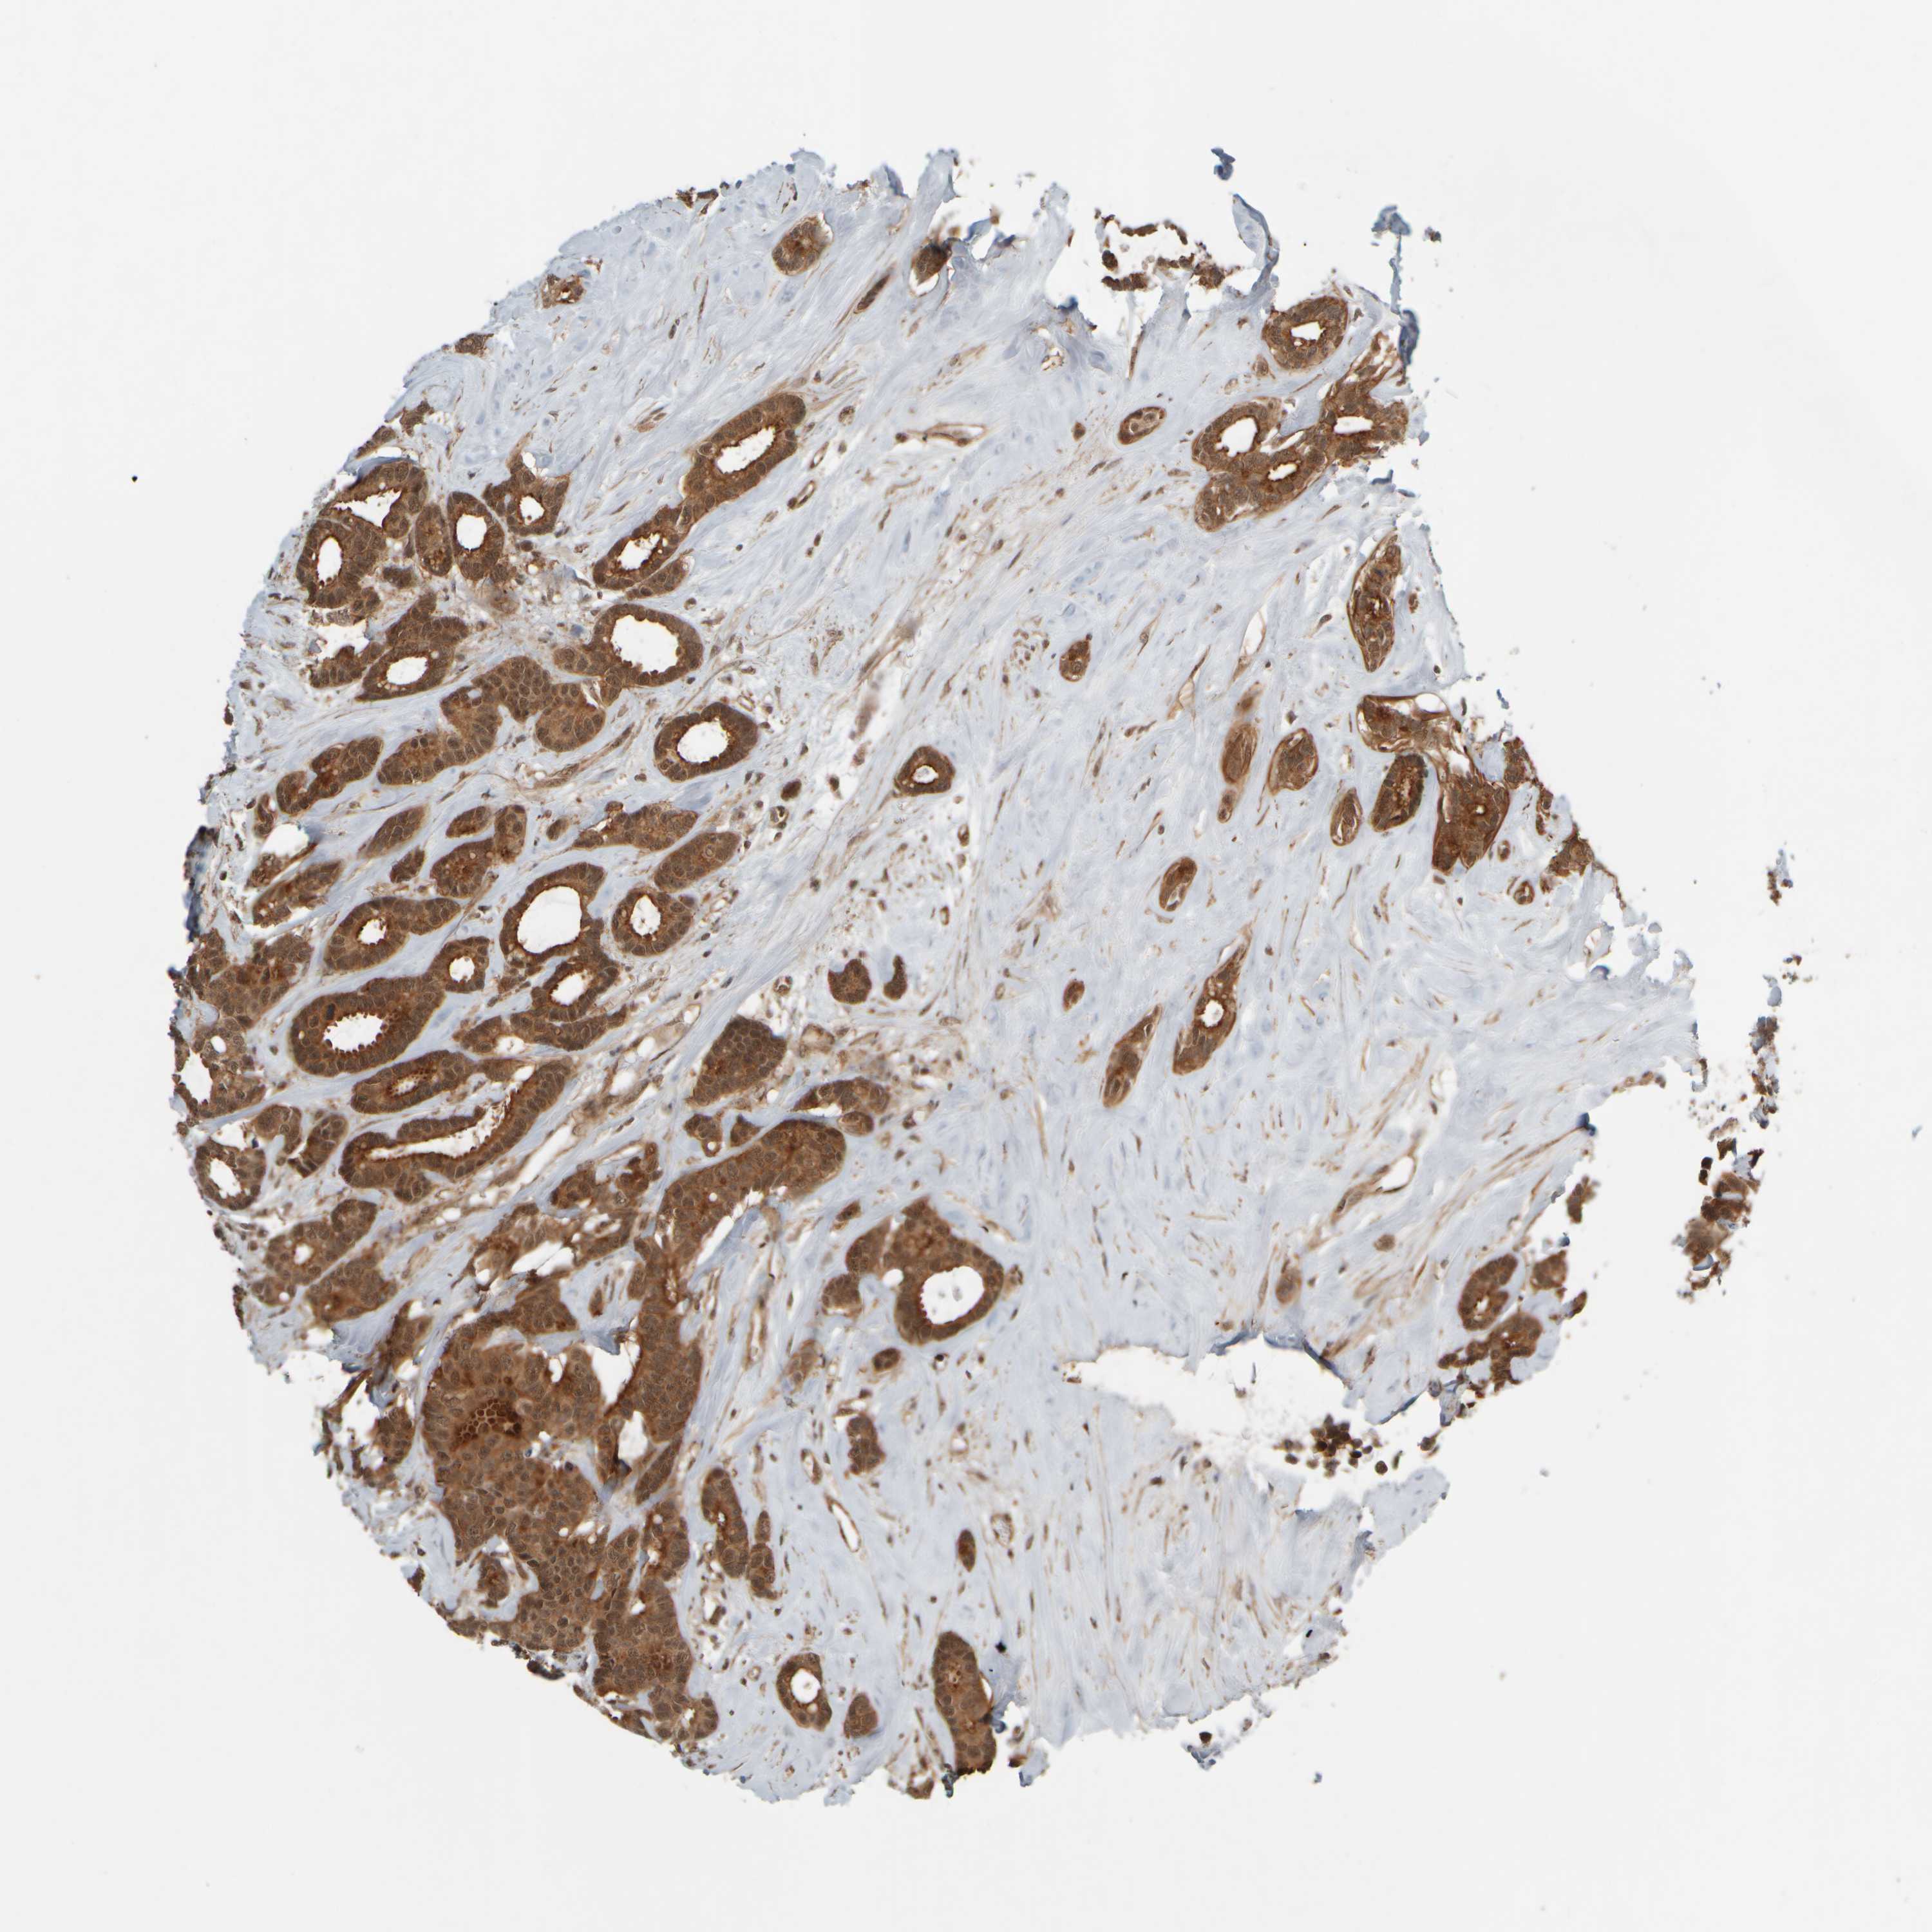

CANCER BREAST CANCER Show tissue menu

BRCA TCGA BRCA VALIDATION PROTEIN EXPRESSION